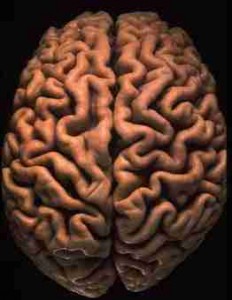

Anak Autis Punya Otak Lebih Besar

TRIBUNJAMBI.COM - Anak-anak penyandang autisme ternyata memiliki ukuran otak yang sedikit lebih besar

Penelitian terbaru yang dimuat jurnal Archives of General Psychiatry edisi Mei ini menyebutkan, perbedaan di antara kedua ukuran ini tampaknya berkaitan dengan rata-rata peningkatan pertumbuhan otak sebelum anak berusia 2 tahun.

Para ahli dari University of North Carolina Amerika Serikat, yang mengagas riset tersebut, menekankan walaupun dari sisi ukuran terus bertambah, tetapi dari segi pertumbuhan tidaklah demikian.

Pada 2005, para ahli meneliti sekelompok anak berusia 2 tahun , dan menemukan bahwa seorang anak pengidap autisme memiliki otak dengan ukuran 5% hingga 10% lebih besar dibandingkan anak yang tidak mengalami gangguan tersebut.

Para ahli belum lama ini melakukan pemeriksaan terhadap kelompok anak yang sama setelah mereka menginjak usia 5 tahun. Para psikiatri melakukan scan otak ulang pada 38 anak pengidap autisme dan 21 anak non autisme. Hasilnya menunjukkan bahwa anak autistik masih memiliki ukuran otak yang sedikit lebih besar, tetapi tetapi ukuran pertumbuhannya sama dengan kelompok anak yang tidak mengidap autisme.

Menurut pimpinan riset Joseph Piven, MD, temuan ini dapat memberikan pemahaman lebih baik tentang gen-gen yang memicu autisme, yang pada gilirannya akan membuka jalan bagi penemuan cara identifikasi secara dini dan pengobatan yang tepat untuk kondisi kelainan ini. (Xinhua)